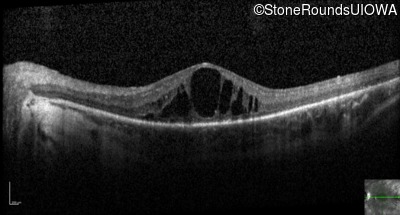

Optical Coherence Tomography - Right - 20/80 +2

Exemplar / OCT Stack